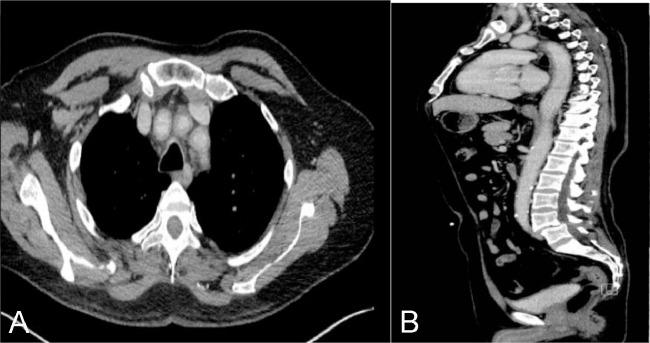

Giant cell arteritis (GCA) is a rare form of large and medium vessel vasculitis affecting about 20 cases per 100,000 persons older than the age of 50 years. GCA results in inflammation and constriction of the temporal arteries, cranial arteries, the aorta, and its major branches. Patients often present with vague constitutional symptoms and fever of unknown origin. GCA is a medical emergency requiring prompt diagnosis and early treatment with glucocorticoids which is essential to avoid irreversible end organ damage such as loss of vision, stroke and aneurysm formation. We report a case of a 63-year-old male patient presenting to our healthcare facility with sudden loss of vision and an ischemic brain infarct to be finally diagnosed as a case of giant cell arteritis with positron emission tomography-computed tomography imaging used to evaluate the full extent of the involved vasculature. Diagnostic imaging with FDG positron emission tomography-computed tomography can play a crucial role in the diagnosis, evaluation of the full burden of the disease and follow up to the response of therapy.

巨细胞动脉炎(GCA)是一种罕见的大中血管血管炎,在50岁以上人群中,每10万人中约有20例发病。GCA会导致颞动脉、颅动脉、主动脉及其主要分支发生炎症和狭窄。患者常出现不明原因的全身症状和发热。GCA是一种医疗急症,需要迅速诊断并尽早使用糖皮质激素治疗,这对于避免不可逆转的终末器官损害(如视力丧失、中风和动脉瘤形成)至关重要。我们报告一例63岁男性患者,因突然视力丧失和缺血性脑梗死前来我院就诊,最终经正电子发射断层扫描-计算机断层扫描成像确诊为巨细胞动脉炎,该成像用于评估受累血管系统的全貌。使用氟代脱氧葡萄糖正电子发射断层扫描-计算机断层扫描进行诊断成像在疾病的诊断、评估疾病的整体负担以及随访治疗反应方面可发挥关键作用。